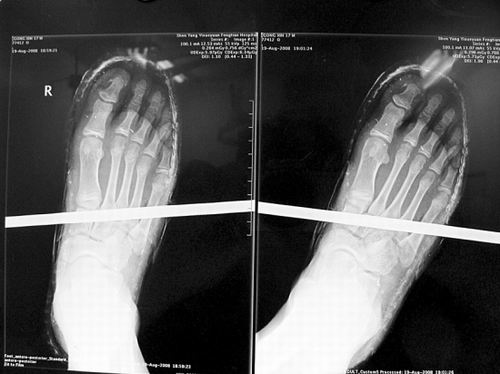

X光片顯示無大礙

事發(fā)時男孩穿著一雙布鞋,骨外二科陳賓醫(yī)生操起剪刀,將布鞋一塊塊剪掉。經(jīng)X光透視,醫(yī)生驚奇地發(fā)現(xiàn):男孩雖然被鋼筋穿透了右腳,但骨頭、大的血管和神經(jīng)都沒受任何傷害!

20日,記者從X光片子上看到,鋼筋避開了男孩腳掌骨頭密集的部位,而是從腳弓處穿過,這個部位基本上以軟組織為主!罢鏇]想到,太神奇了!”幾名醫(yī)生連聲感嘆,術中,他們分工合作,小心翼翼地將鋼筋取出,并做了引流、清創(chuàng)、包扎。